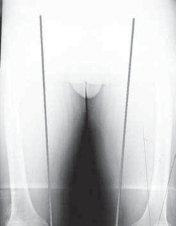

4. Using fluoroscopy, the alignment rod is placed at the center of the femoral head (

TECH FIG 3A

) and then at the center of the ankle joint (

TECH FIG 3B

).

A B F

D E TECH FIG 3•A.

Fluoroscopic image of alignment rod through femoral head.

B.

Fluoroscopic image of the alignment rod in the center of the ankle.

C.

The subsequent location of the alignment rod in the knee. This initial mechanical axis must be corrected. It should match with the preoperative planning.

Fluoroscopic image verifying the two guide pins placed from medial to lateral using the osteotomy guide pin assembly. Note how in this view, which is parallel to the joint surface, the two pins are superimposed on one another, thus verifying that they, too, are parallel to the joint surface.